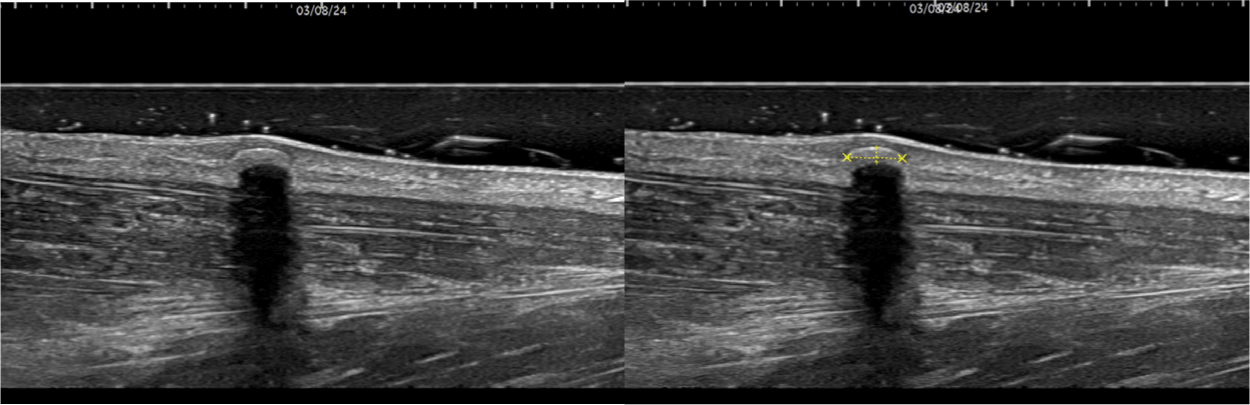

초음파 상 소견 : 2024년 3월 8일 초음파기기(GE;general electronics사 P9)를 활용하여 Anterior tibialis의 피부병변에 longitudinal view로 probe를 잡고 영상을 촬영하였다. 사용된 probe는 linear probe로 ML6-15이며 15㎒로 setting하여 측정하였다. 초음파 영상에서 최상단에 가로 0.36㎝, 깊이 0.1㎝ 크기의 매끄러운 결석 경계면을 확인할 수 있었다. Acoustic shadow로 후방음영 및 clean shadow가 관찰되었다(Fig. 2).

모기질종은 초음파에서 잘 구분되는 둥근 형태의 불균질한 상으로 나타나며, 이는 병소 내에 낭종화된 무향 부위(anechoic area)와 점상으로 분포하는 석회화물에 기인하며19), 일반적으로 조직검사와 방사선학적 검사를 통해 정확한 진단이 이루어진다. 본 증례는 초음파에서 석회화가 관찰되었으며 피부 종양 중 초음파 상 석회화를 보이는 대표적인 질환으로는 모기질종, 피부석회증 등이 있다. 피부석회증은 피부 조직 내 비정상적인 calcium 축적으로 인한 질환이며, 모기질종과 무통성, 석회화, 결절의 형태를 띠는 공통점이 있어 감별이 필요하다.